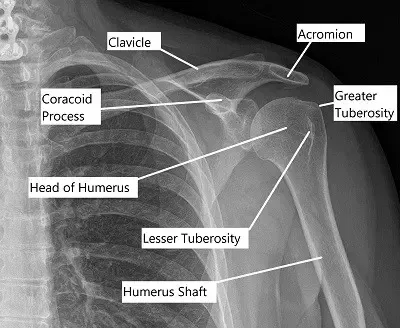

Anteroposterior view of Left Shoulder.

The Glenohumeral or the real shoulder joint is made up of the articulation of the ball of the head of the arm bone called the humerus into the cup of the shoulder blade called the scapula.

The cup makes only 1/8th of the circumference of the shoulder and hence the shoulder joint is seemingly unstable, especially if compared to other large ball and socket joints of the body that is the hip joint. The joint can be involved in arthritis and well as fractures and sprains